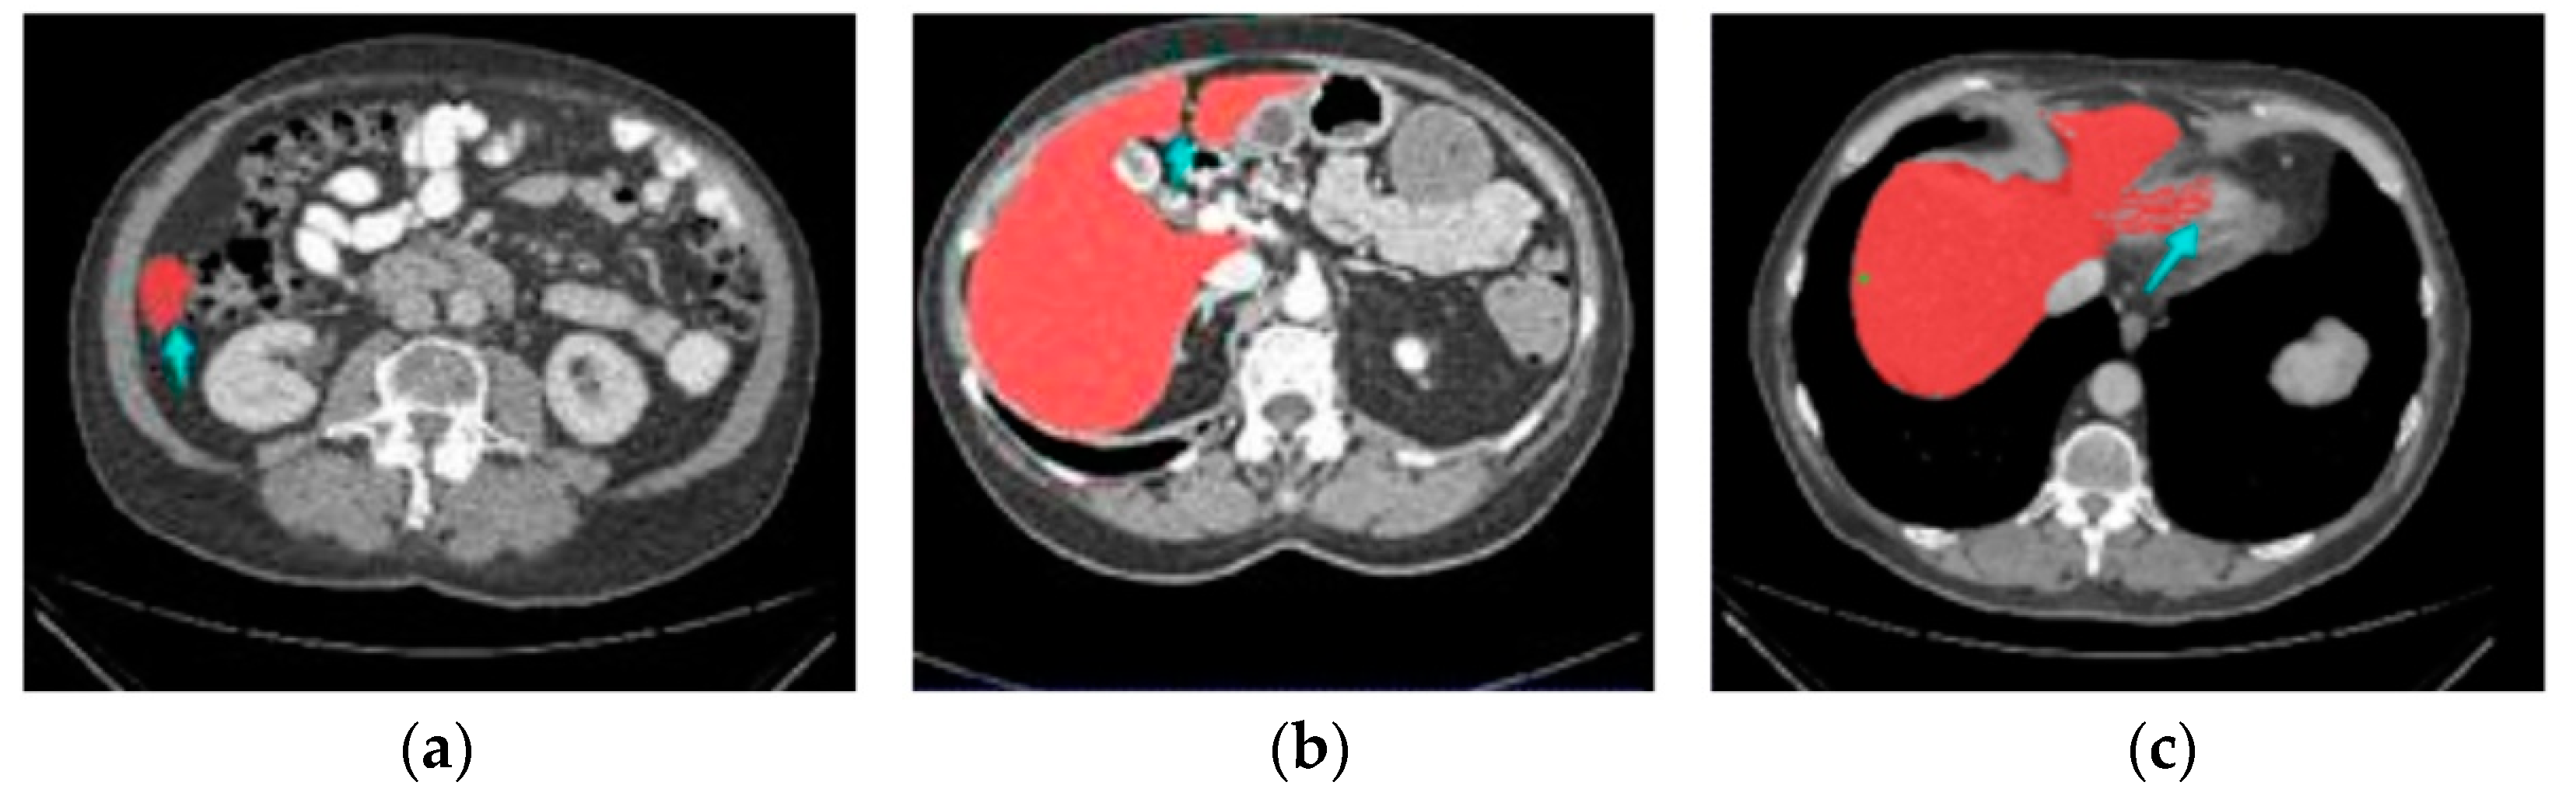

4.1. Segmentation Results